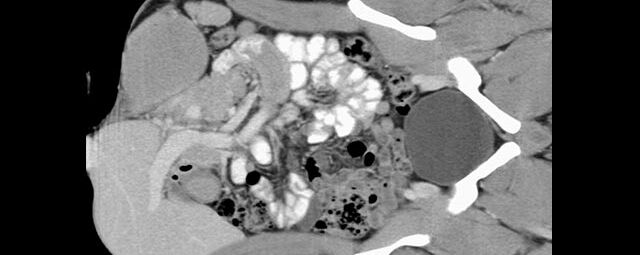

Abdomen (Bauch und Becken)

• Diagnostik von entzündlichen und tumorösen Erkrankungen der Bauchorgane

• Diagnostik von akuten Notfällen wie Darmverschluss, Hohlorganperforation oder Traumafolgen

• Darstellung der großen Gefäße zur Erkennung von Gefäßverschlüssen (z. B. Mesenterial - Arterienembolie oder Einengungen von Gefäßen (z. B. Nierenarterien)

• Darstellung und Therapieplanung von Aneurysmen (CT- Angiographie)

• Virtuelle Kolonographie zur Darstellung des Dickdarmes z. B. bei Kontraindikation zur Darm-Spiegelung oder nur unvollständig durchführbarer Koloskopie.

Sollte Kontrastmittel intravenös verabreicht werden, geschieht dies ohne wesentlichen Zeitverlust während der Untersuchung. Dazu wird dann auf der Untersuchungsliege eine Kanüle in die Armvene platziert.

Das Kontrastmittel wird während der Bewegung der Liege über einen Injektor in die Vene gespritzt, der die erforderliche KM-Menge in einer genau bestimmten Zeit und Geschwindigkeit in den Körper einbringen kann.

In manchen Fällen – vor allem bei der Untersuchung von Hals, Thorax und Abdomen – reicht das Darstellungsvermögen des Gerätes allein nicht aus, deshalb werden kontraststeigernde Mittel, sog. Kontrastmittel, in das Blut (zum Darstellen oder Abgrenzen von Gefäßen oder auch zur Unterscheidung von gesundem und krankem Gewebe) oder auch zum Trinken (zur besseren Abgrenzung des Magen-Darm-Traktes) verabreicht.

• Intravenöses Kontrastmittel:

Es handelt sich hierbei um gut verträgliche jodhaltige Substanzen, die Ihnen über eine Kanüle während der Untersuchung in eine Armvene injiziert werden. Dies geschieht über einen sogenannten Injektor, der eine bestimmte Menge Kontrastmittel in einer vorgegeben Zeit verabreicht, welche genau für die spezielle Fragestellung berechnet wurde.